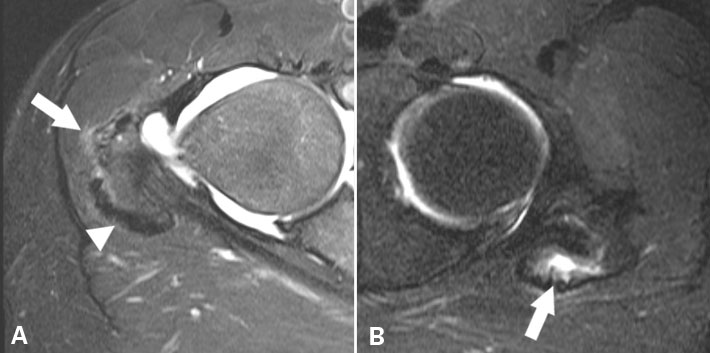

磁共振呢是近代医学检查技术一次,革命性的突破,有了它我们对很多疾病就有了一个更新的认识,因为核磁共振不但能够显示骨质的结构,还能显示软骨血管,神经,肌肉,筋膜,滑膜,关节囊等等。

核磁共振呢,对于很多疾病的一些早期判断还是挺有用的。比如说骨头坏死的早期,这时候通过x光或者CT可能都看不出来,只有通过核磁共振才能够表现出早期的一个水肿信号。

但是由于核磁共振是一种非常敏感的检查,很多疾病在早期都会表现为一个同样的表现,从鉴别上就会出现一定的问题,比如说很多问题都会造成髋关节产生滑膜炎,出现积液,但是其实搞不清楚这些滑膜炎积液到底是什么性质来的。